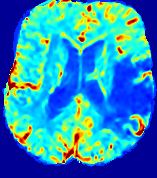

Slice #1Slice #2Slice #3Slice #4Slice #5Slice #6𝐕gt𝟐subscriptnormsuperscript𝐕gt2\|\bf{V}^{\text{gt}}\|_{2}Refer to captionRefer to captionRefer to captionRefer to captionRefer to captionRefer to caption𝐕est𝟐subscriptnormsuperscript𝐕est2\|\bf{V}^{\text{est}}\|_{2}Refer to captionRefer to captionRefer to captionRefer to captionRefer to captionRefer to captionRefer to caption1.51.51.51.21.21.20.90.90.90.60.60.60.30.30.30.00.00.0(mm/s)𝑚𝑚𝑠(mm/s)Destsuperscript𝐷estD^{\text{est}}Refer to captionRefer to captionRefer to captionRefer to captionRefer to captionRefer to captionRefer to caption0.0150.0150.0150.0120.0120.0120.0090.0090.0090.0060.0060.0060.0030.0030.0030.0000.0000.000(mm2/s)𝑚superscript𝑚2𝑠(mm^{2}/s)

Figure 14: PIANO identifiability testing: advection imaging via advection-diffusion. Top row shows 𝐕gt2subscriptnormsuperscript𝐕gt2\|{\bf{V}}^{\text{gt}}\|_{2} used for simulating ground truth pure advection. Rows below show the estimated 𝐕est2subscriptnormsuperscript𝐕est2\|{\bf{V}}^{\text{est}}\|_{2} and Destsuperscript𝐷estD^{\text{est}} on corresponding slices. Note that the plotted value scale for Destsuperscript𝐷estD^{\text{est}} is 0.01 of that for 𝐕gt2subscriptnormsuperscript𝐕gt2\|{\bf{V}}^{\text{gt}}\|_{2} and 𝐕est2subscriptnormsuperscript𝐕est2\|{\bf{V}}^{\text{est}}\|_{2}.

We use the same ‘Advection Imaging’ simulation of Sec. 4.2.1 as the concentration dataset for PIANO. However, instead of modeling pure advection (Eq. 15), we let PIANO estimate both velocity 𝐕estsuperscript𝐕est{\bf{V}}^{\text{est}} and diffusivity Destsuperscript𝐷estD^{\text{est}} via the advection-diffusion PDE (Eq. 2) underlying the proposed PIANO model. Fig. 14 shows the estimated 𝐕est2,subscriptnormsuperscript𝐕est2\|{\bf{V}}^{\text{est}}\|_{2}, and Destsuperscript𝐷estD^{\text{est}} fields for one patient. Although PIANO has the freedom to estimate both a velocity and a diffusivity field from pure advection, PIANO differentiates well between advection and diffusion: the estimated 𝐕est2subscriptnormsuperscript𝐕est2\|{\bf{V}}^{\text{est}}\|_{2} successfully reproduces the ground truth 𝐕gt2subscriptnormsuperscript𝐕gt2\|{\bf{V}}^{\text{gt}}\|_{2} governing the simulated advection process, just as it already did in the ‘Advection Imaging via Advection’ test (Fig. 12). More importantly, the estimated diffusivity Destsuperscript𝐷estD^{\text{est}} is orders of magnitudes smaller than 𝐕est2subscriptnormsuperscript𝐕est2\|{\bf{V}}^{\text{est}}\|_{2}, indicating the estimated diffusion is negligible compared to the estimated advection, which is highly consistent with the underlying pure advection of the simulated data.